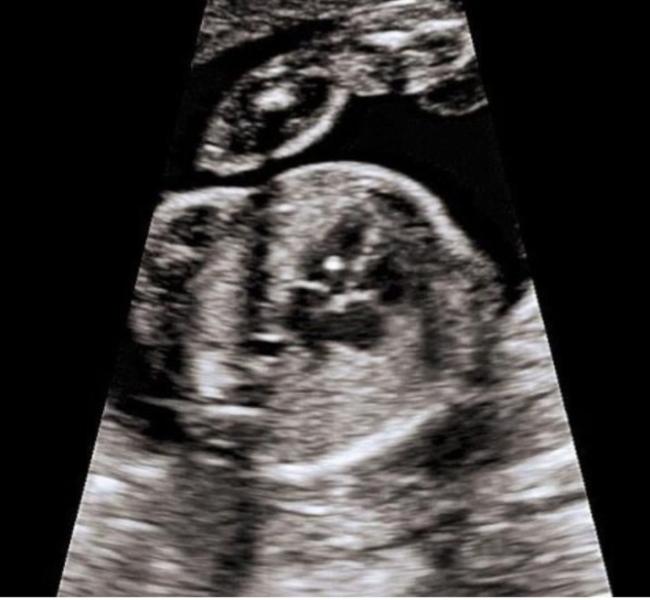

Вчера были на втором скрининге 19.5 недель )

Все хорошо малышок был очень активный😄 но стеснительный не удалось посмотреть кто там

Единственное на узи было увиденна белая точечка в левом желудочке .Узист сказала ,что ничего страшного на 3 скрининге должно уже пройти .А я что-то нервничаю 😔

Врач тоже сказала,что ничего страшного. Надеюсь пройдет ,у кого так было ?